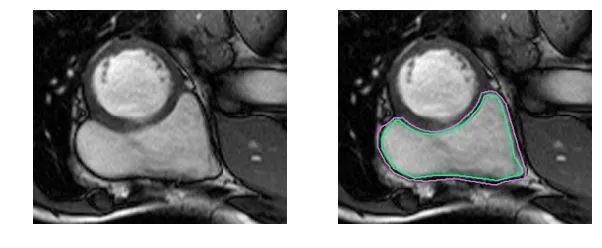

下面用几组图片来感受一下这种分割问题的困难。下图是右心室的MRI图片:

基于FCN网络结构实现左、右心室分割:

Phi V. T.. A Fully Convolutional Neural Network for Cardiac Segmentation in Short-Axis MRI[C]. CVPR 2016.